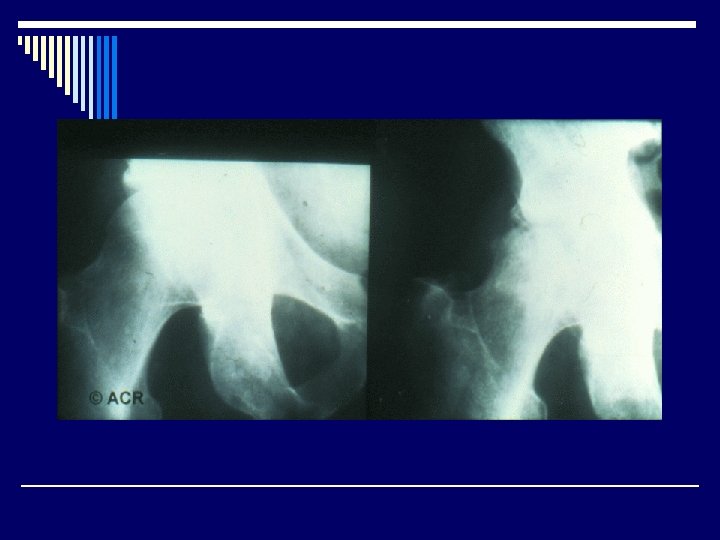

Radiological features o Joint effusion o Erosion o Joint space narrowing o Joint deformity o Osteoporosis o Bony ankylosis